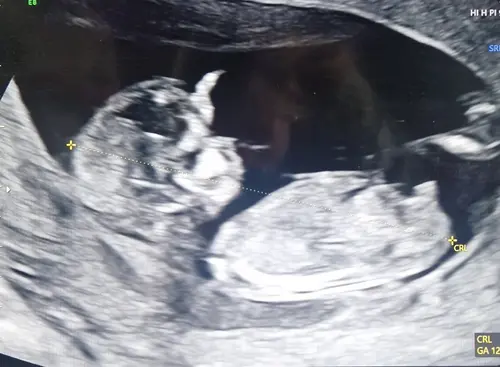

Jongen of meisje? 🩷🩵 13 weken vandaag

Ik denk jongen

Ik denk ook jongen 🩵

Hij of zij ligt zo in een kommetje. Ik vind het lastig om te zien. Is iemand hier misschien heel goed in hihi.